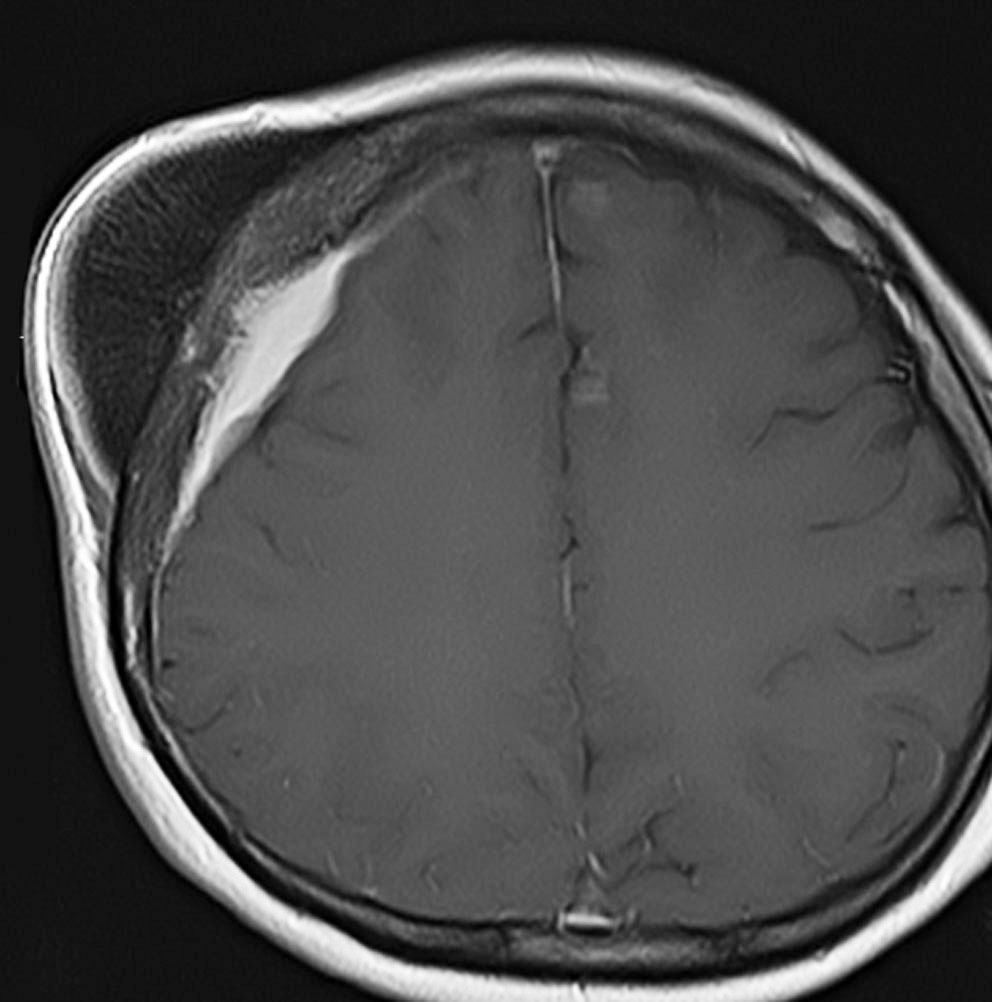

上矢状洞髄膜腫 superior sagittal sinus meningioma

上矢状洞を埋め尽くすように増大して,頭蓋骨浸潤が著しい髄膜腫ですが,ごく軽度の右足脱力以外に何の症状もありません。上矢状洞はゆっくり閉塞すれば,このような頭頂部から後頭部にわたる広範閉塞でも,静脈還流に障害がない場合が多いといえます。大脳の前半部の血流は前頭葉表面の皮質静脈から海綿静脈洞に側副路を形成しています。頭蓋内圧亢進所見もなく,これらはこの髄膜腫がゆっくり増大したということを示唆しています。

手術直後の画像です。全部いっぺんに摘出するのは無理なので,まず前から80%くらいの腫瘍を摘出しました。肥厚した骨はチタンプレートで置き換えてあります。後頭部の上矢状洞内と大脳鎌に少し残りましたが,この6ヶ月後に2回目の開頭術をして全摘出しました。結果的にこの例では,上矢状洞を冠状縫合のあたりから,静脈洞交会まで壁ごと全部摘出しましたが,脳浮腫も何も生じませんでした。腫瘍の両側にある皮質静脈 cortical veinsを損傷しないことが肝要です。

右の病理像は,頭蓋骨浸潤している部分 ですが,骨破壊は良性髄膜腫に特徴的な骨内浸潤像です。この骨浸潤像は悪性像とはいえません。MIB-1は高いところで8%、低いところで3%程度です。